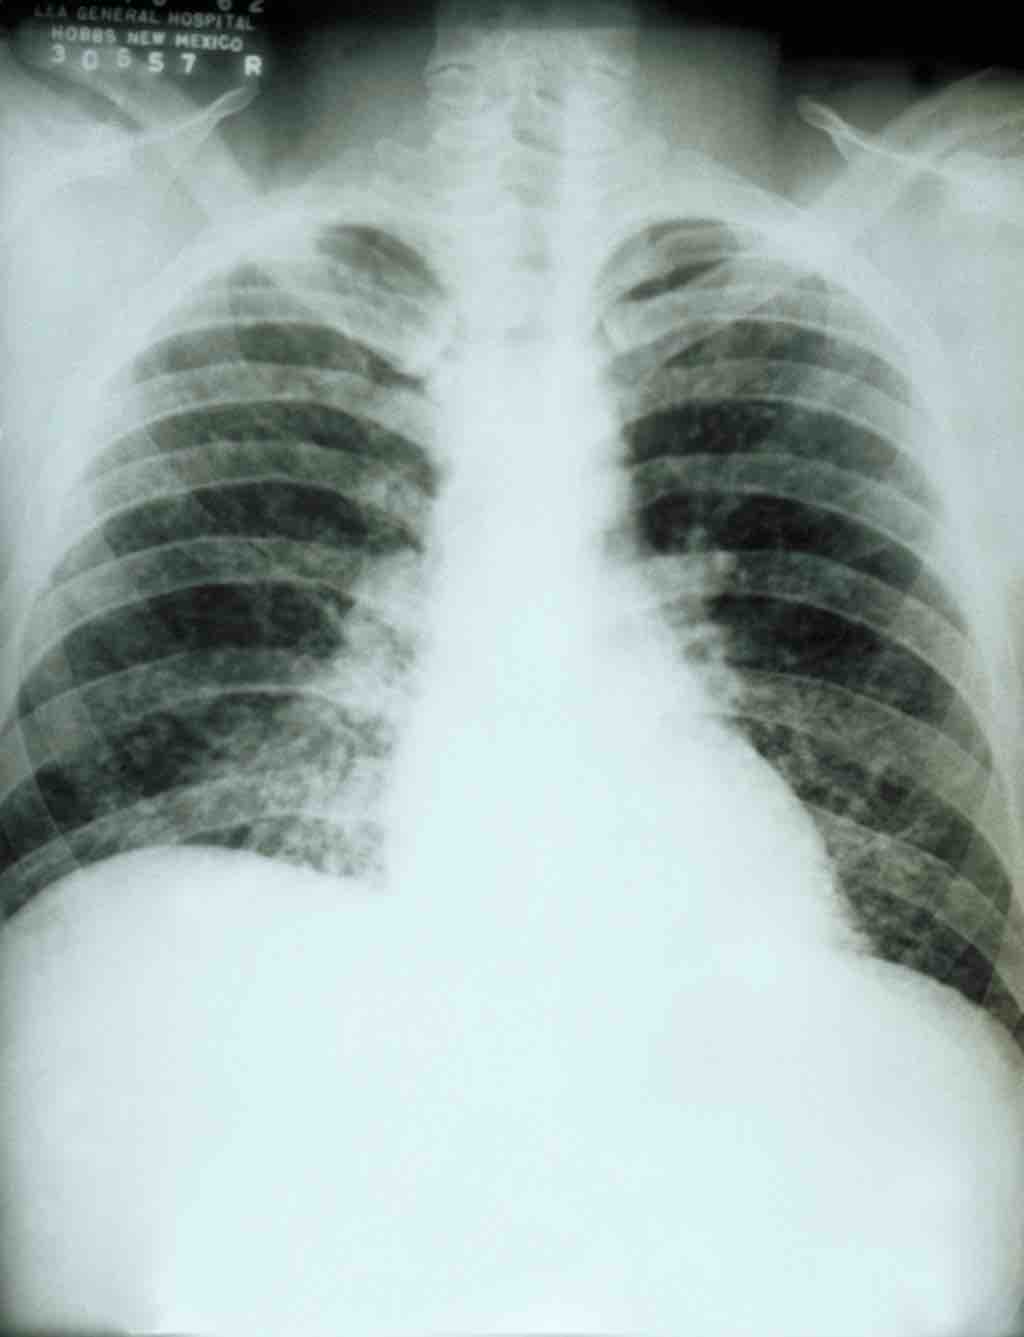

Histoplasmosis

Acute pulmonary histoplasmosis

This is a chest X-ray of a patient with acute pulmonary histoplasmosis.